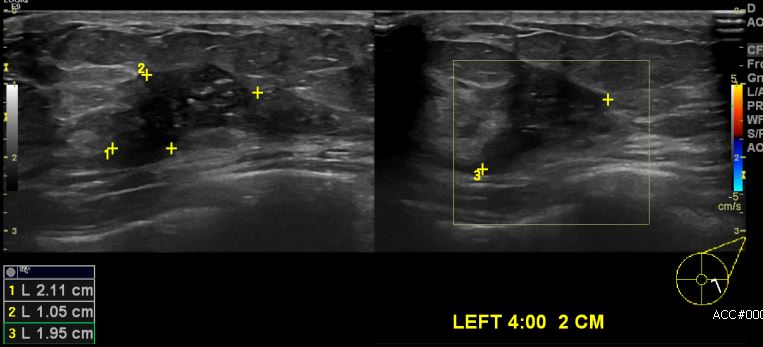

상기환자 건강검진상 이상소견으로 내원하신 50대 여성분으로 좌측유방 4시 방향에서 2cm 떨어진 거리에 의심스러운 멍울 조직검사 시행하여 좌측 침윤성유관암 진단 되었습니다.